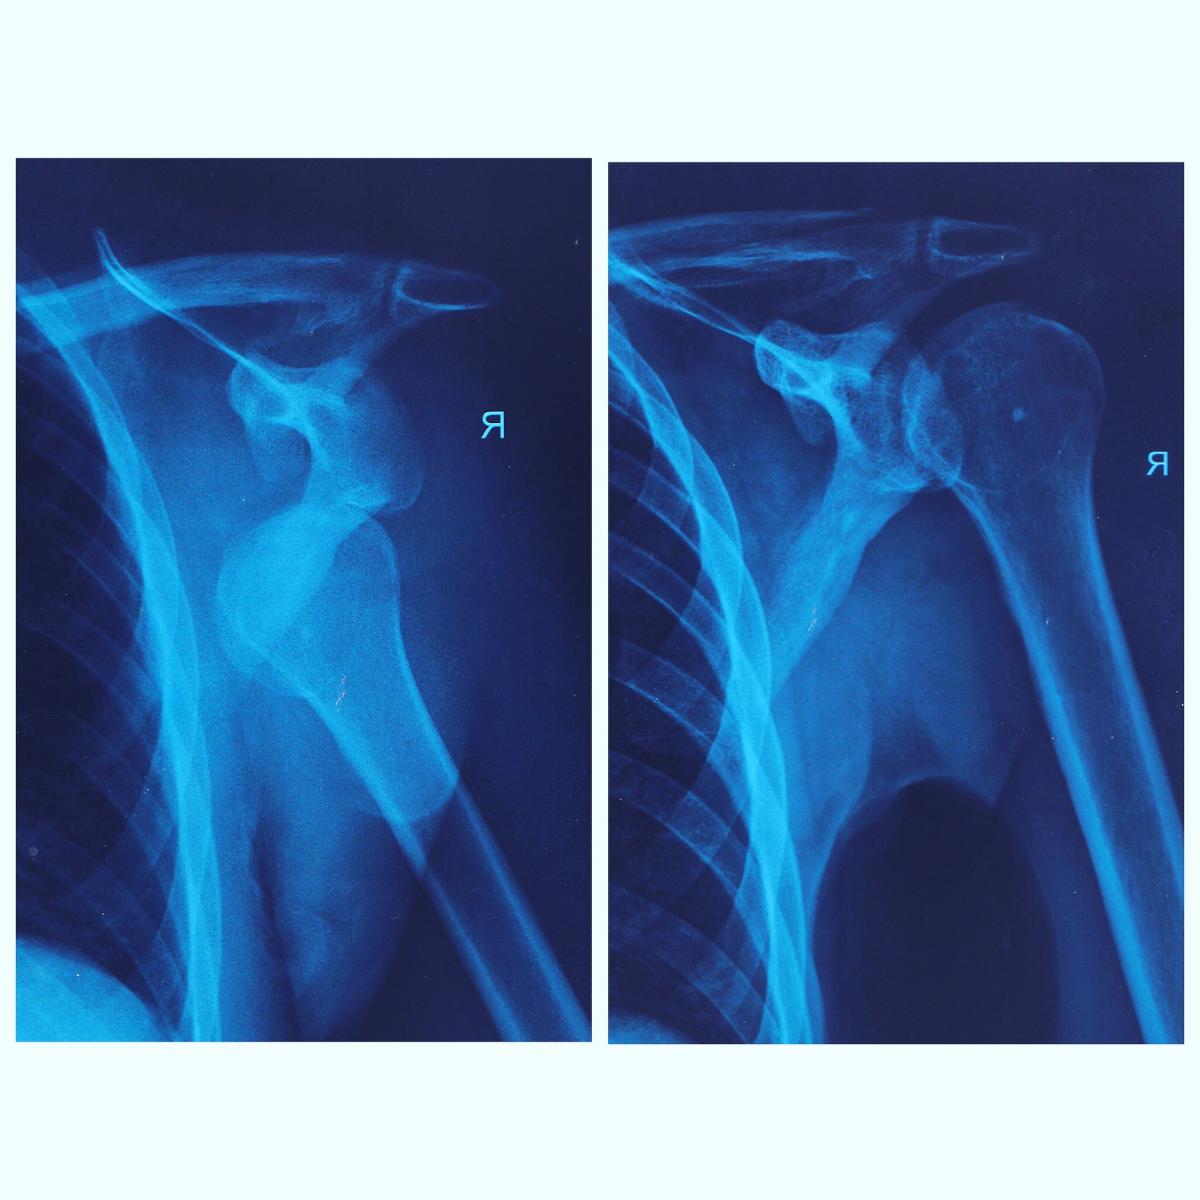

Весёлые картинки?

Мой муж и без риска справился ... споткнулся б..дь, дома. Две недели вот прошло. Надеюсь до зимы снова топать будет...

Бывает, чо)Весёлые картинки?

Со мной в палате лежал чел из Таганрога. Он к дедушке с бабушкой в Москву приехал на пару дней. Спустился в магаз, что у него в доме за хлебом. Подскользнулся, упал о бордюр и так ацки себе руку сломал, что её только на штифт собрать смогли. Сходил, бл.. за хлебушком) вот это реально обидно.

П.с. ещё одного привезли с таким же как у меня (прям точь в точь) с Сорочан. Ему крепы в прокате на 8 накрутили, а он до этого пару раз всего пробовал на учебной горке.